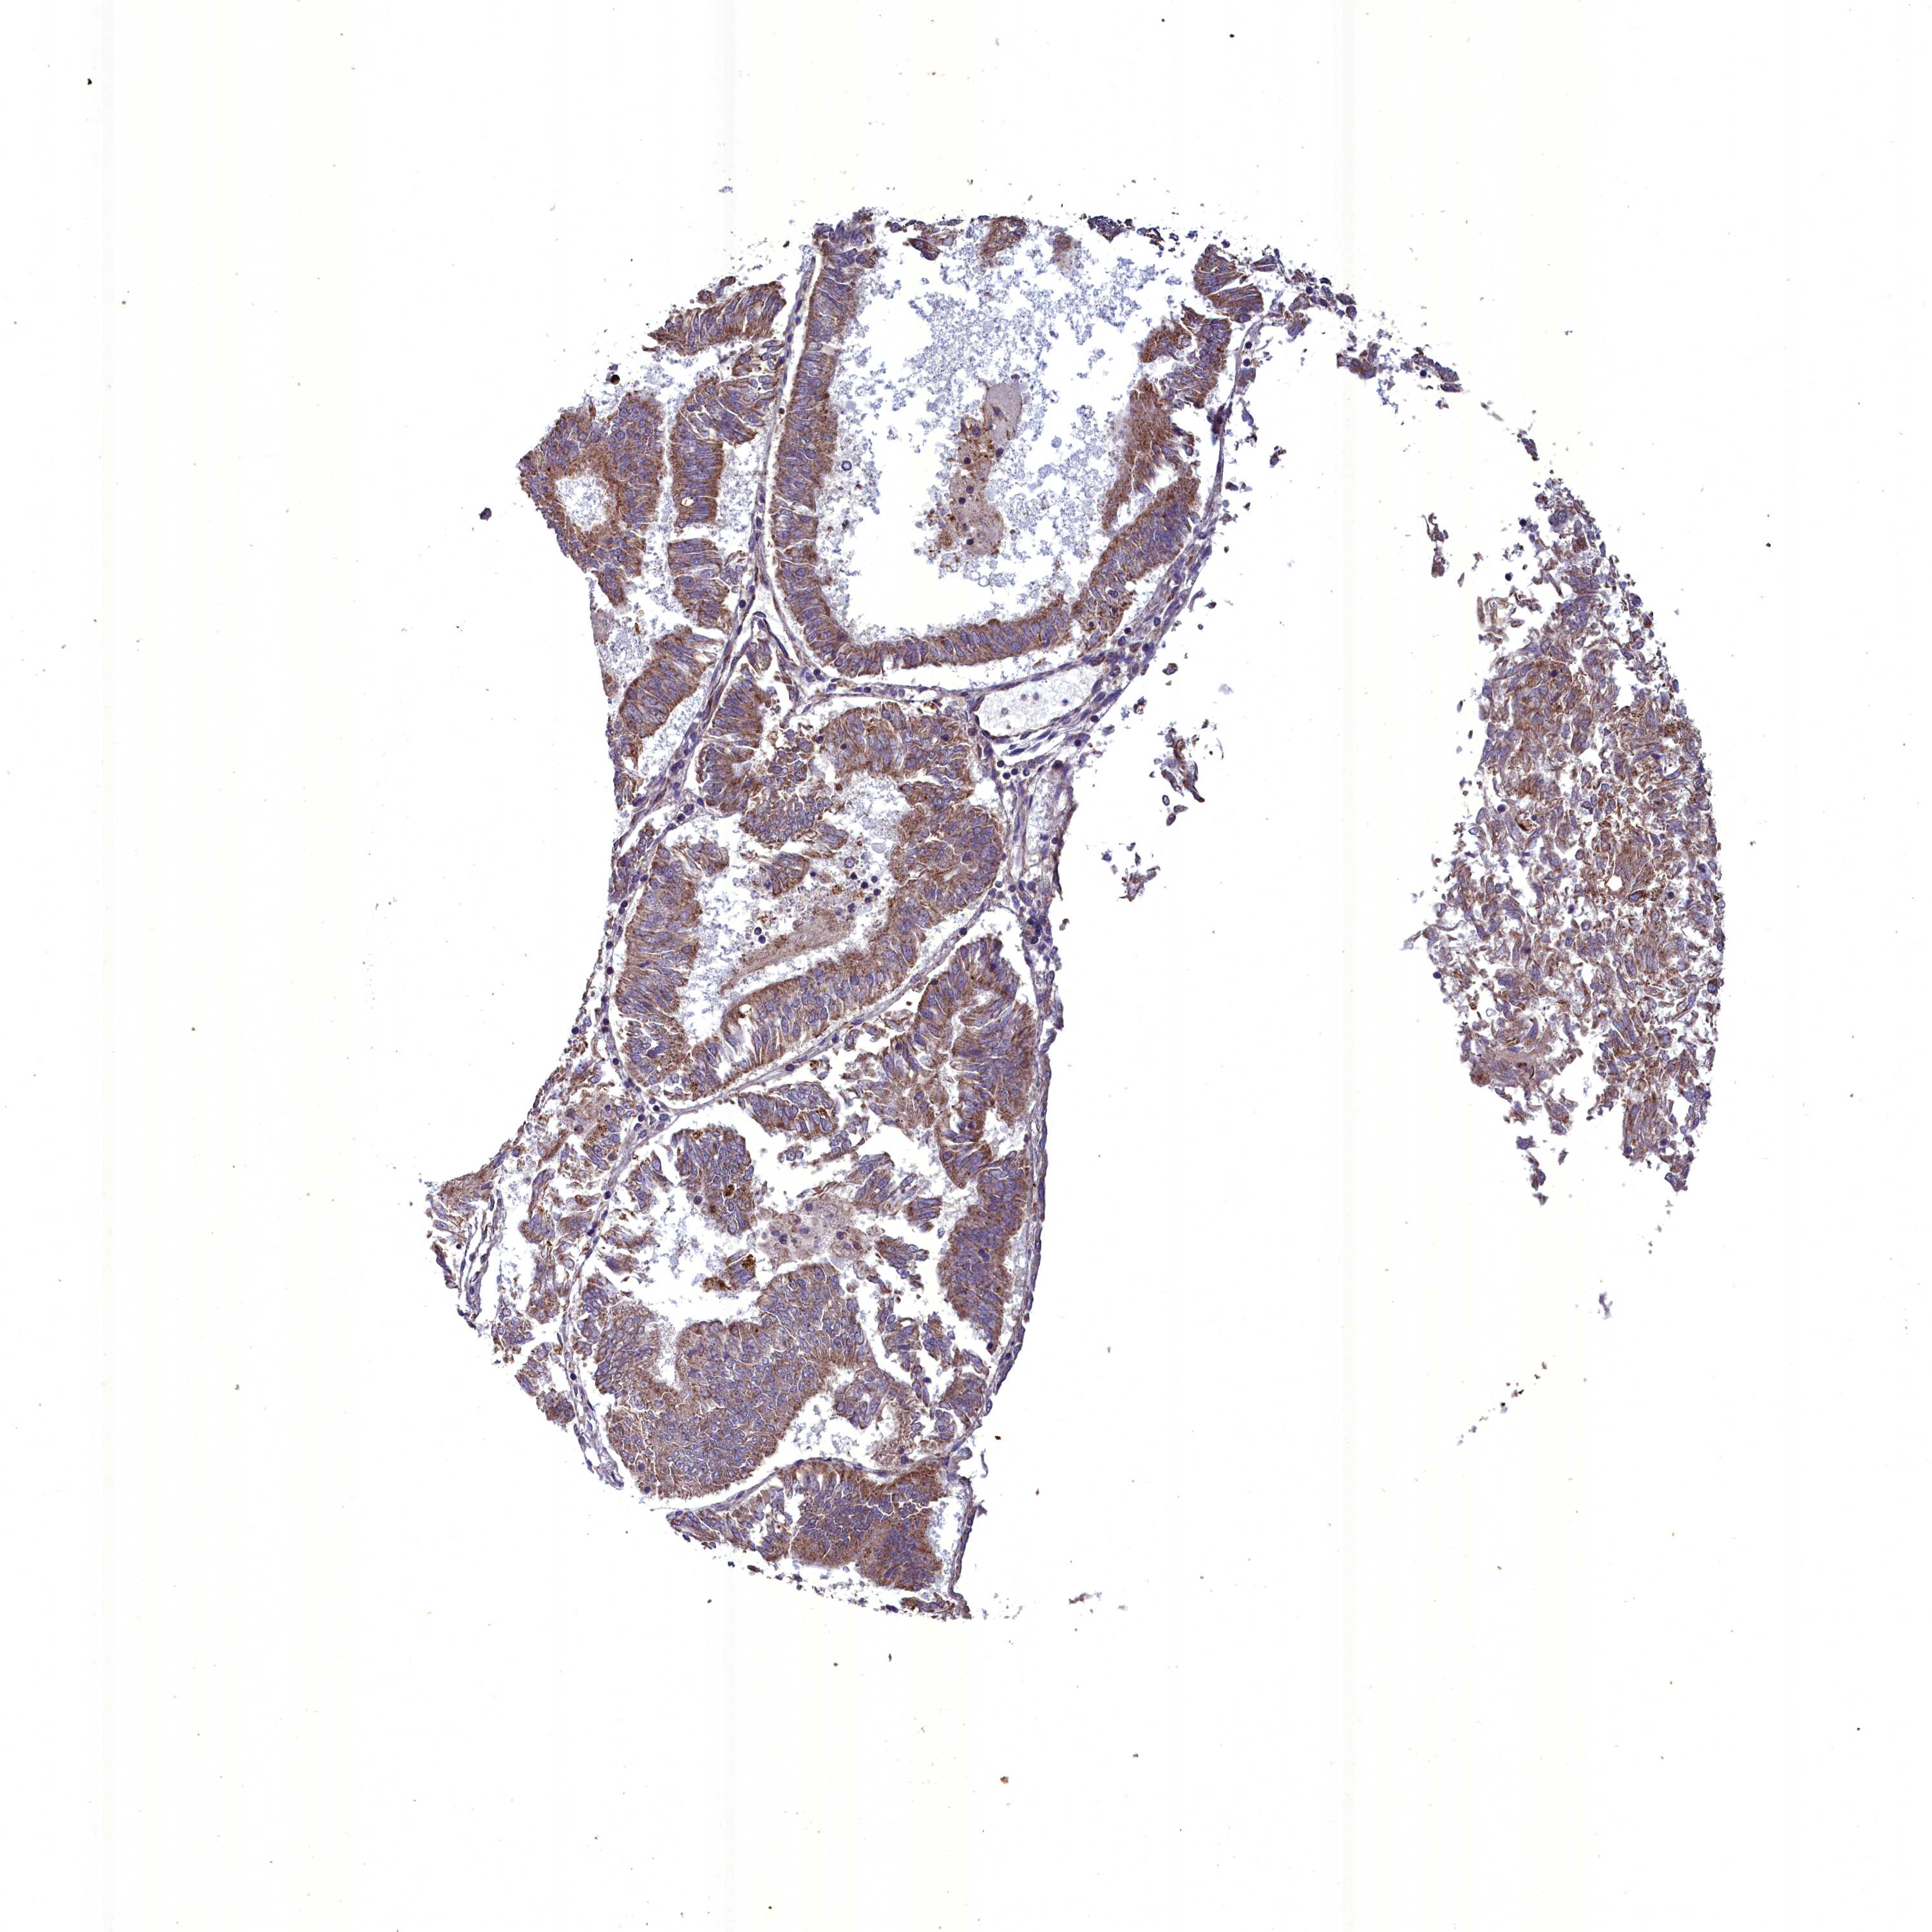

ENDOMETRIAL CANCER - Protein expressioni

A mouse-over function shows sample information and annotation data. Click on an image to view it in a full screen mode. Samples can be filtered based on level of antibody staining by selecting one or several of the following categories: high, medium, low and not detected. The assay and annotation is described here.

Note that samples used for immunohistochemistry by the Human Protein Atlas do not correspond to samples in the TCGA dataset.

Antibody stainingi

Antibody staining in the annotated cell types in the current human tissue is reported as not detected, low, medium, or high, based on conventional immunohistochemistry profiling in selected tissues. This score is based on the combination of the staining intensity and fraction of stained cells.

Each image is clickable and will lead to virtual microscopy that enables deeper exploration of all samples and also displays staining intensity scores, fraction scores and subcellular localization as well as patient and tissue information for each sample.

Antibody HPA040689

Antibody HPA043903

Staining

High

Medium

Low

Not detected

Intensity

Strong

Moderate

Weak

Negative

Quantity

>75%

75%-25%

<25%

None

Location

Nuclear

Cytoplasmic/membranous

Cytoplasmic/membranous,nuclear

Adenocarcinoma, NOS